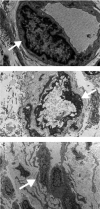

Figure 2

Transmission electron microscopy. A. Control skin specimen shows a dermal capillary with thin basement membrane (arrow) and flattened endothelial cell. B. Capillary from a scleroderma case shows mild lamellation (arrow) of the basement membrane. C. A more extensive lamellation (arrow) of the basement membrane can be seen. The endothelial cells show abundant cytoplasm and enlarged nuclei.